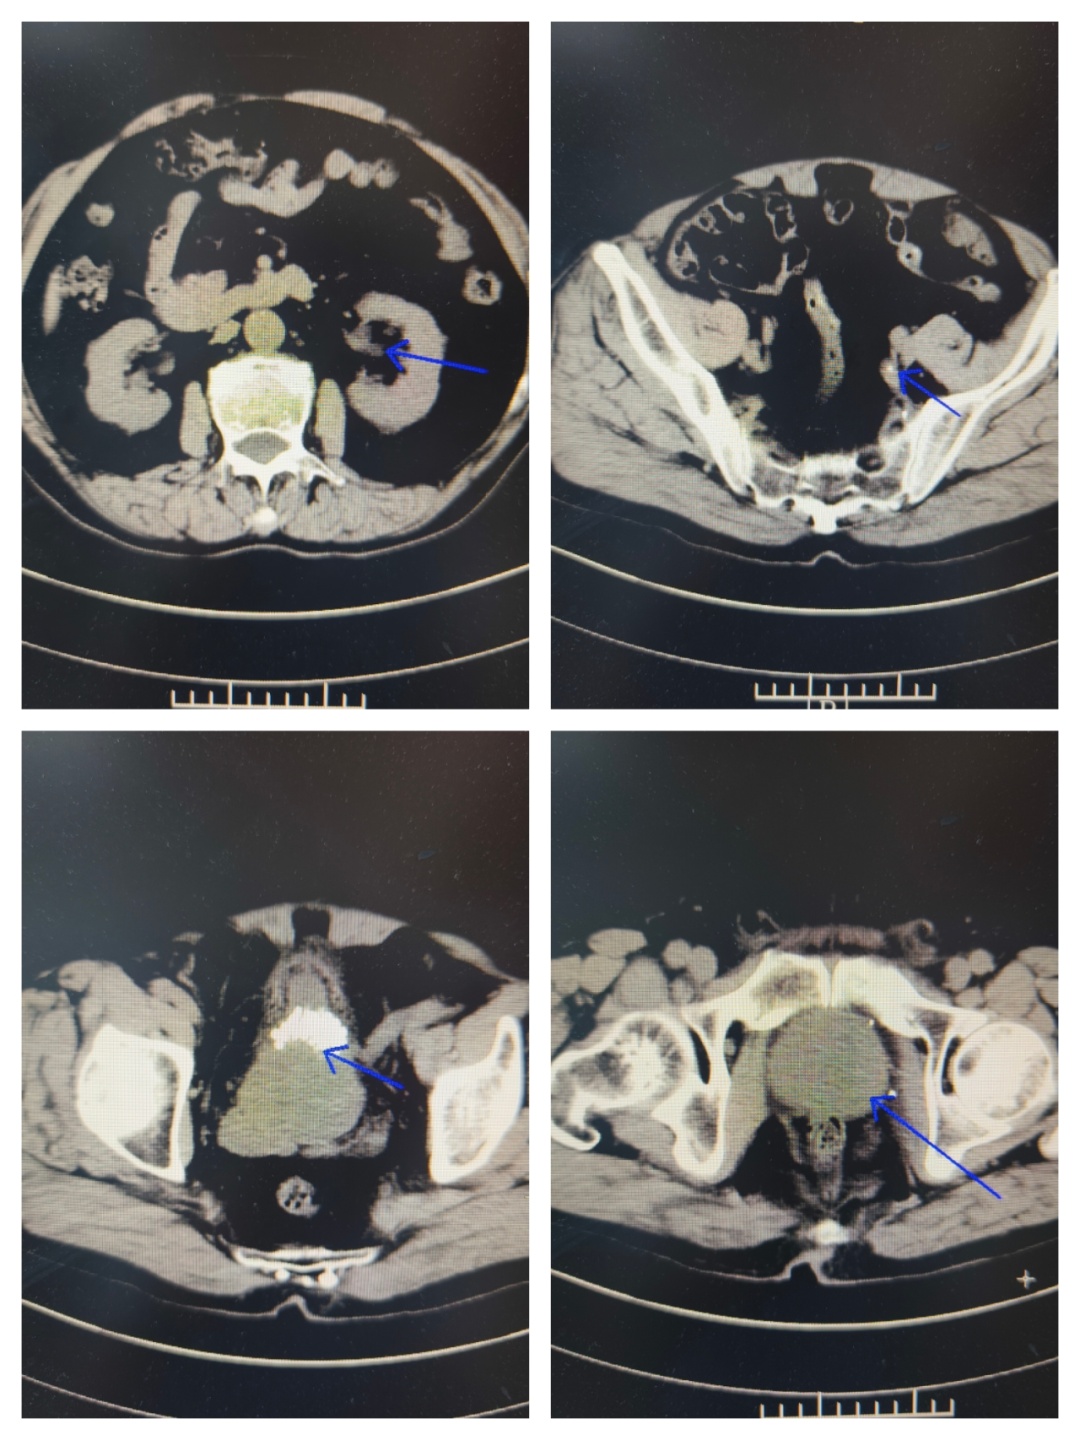

病情介绍 患者张先生(化名),77岁,因“尿频、尿急、尿痛伴血尿1天”来我院急诊。患者痛苦面容,自觉排尿困难且伴有肉眼可见的红色尿液,严重影响生活质量。 经检查发现,患者存在以下泌尿系统问题: 1.右侧输尿管结石伴有肾积水和感染 2.膀胱多发结石 3.前列腺增生 这些疾病相互影响,形成恶性循环:前列腺增生导致排尿不畅,尿液滞留形成膀胱结石;膀胱结石又可能堵塞尿道出口,加重排尿困难;而输尿管结石则阻碍尿液从肾脏排出,引起肾积水和感染,严重时可能影响肾功能甚至导致败血症。 治疗过程 面对这一复杂情况,区中医医院泌尿外科团队制定分期手术方案,确保治疗安全有效: 第一期手术:急诊处理,解除危机 手术名称:经尿道输尿管镜下膀胱结石钬激光碎石取石术+右侧输尿管支架置入术(双J管置入) 手术目的: 1.解除感染隐患:置入输尿管支架管,能立即疏通梗阻的右侧输尿管,引流出淤积的感染尿液,迅速控制感染,保护肾功能。 2.清除膀胱结石:同时处理已存在的膀胱结石,缓解部分下尿路症状。 此次手术快速、微创,核心目标是“控制感染、引流减压”,为后续根治性手术创造安全的身体条件和手术窗口期。 第二期手术:根治性处理,经过近两周的抗感染治疗和身体恢复,患者一般情况显著改善。 手术名称:经尿道右侧输尿管镜钬激光碎石取石术+前列腺电切术(TURP)+经尿道右侧输尿管支架置换术 手术目的: 1.粉碎输尿管结石:在支架管引导下,精准粉碎并取出造成梗阻的“元凶”——右侧输尿管结石。 2.切除前列腺:彻底切除增生的前列腺组织,从根源上解除下尿路梗阻,预防结石复发。 3.更换支架:确保输尿管通畅愈合。此次手术一举解决了所有根本性问题。 术后恢复 术后患者恢复顺利: 1.血尿、尿痛等症状消失。 2.困扰已久的尿频、尿急、夜尿增多等症状得到极大改善。 3.复查尿流率检查,结果完全恢复正常。 4.患者对治疗效果非常满意,由衷感谢我科团队精湛的技术和负责任的决策。 此次手术的成功,体现区中医医院处理复杂高危病例的丰富经验和先进理念: 1.精准决策:不盲目追求“一刀切”,而是根据“轻重缓急”原则,制定个体化的分期治疗方案。先解决急性、危及生命的问题(感染梗阻),再处理慢性、根源性问题(结石、前列腺增生),最大程度保障了患者安全。 2.技术的保障:两次手术均采用经尿道的微创方式,利用输尿管镜、电切镜等先进设备,体表无切口,创伤小,恢复快,非常适合高龄患者。 3.围术期管理:完善的术前准备、术中的麻醉配合、细致的术后护理,是患者能够平稳度过两次手术、顺利康复的坚实基础。 奉贤区中医医院 泌尿外科团队 专家提醒,老年男性出现以下症状时应及时就医: ·尿频、尿急、夜尿增多 ·排尿困难、尿流变细 ·血尿 ·腰背部疼痛 早期诊断和合理治疗能够有效保护肾功能,提高生活质量。我院泌尿外科在此类复杂泌尿系统疾病的微创治疗方面积累了丰富经验,为众多患者解除病痛。 王志伟 副主任医师 泌尿外科王志伟副主任医师,毕业于南昌大学医学院,医学硕士。2017年至上海长海医院泌尿外科进修学习、2022年至南昌大学第二附属医院泌尿外科进修学习。获2020年度医院十大好医生、医院优秀员工。主持完成市级科研课题2项,参与完成省级科研课题1项,两篇论文获得市级科协优秀学术论文二等奖。 擅长泌尿系统结石微创治疗,输尿管镜碎石取石术,电子输尿管软镜钬激光碎石负压取石术,彩超引导下经皮肾镜碎石取石术,泌尿系统感染的综合治疗,彩超引导下经会阴前列腺穿刺活检,前列腺增生微创手术,肾囊肿、肾肿瘤及前列腺肿瘤、膀胱肿瘤等泌尿系统肿瘤的诊治及微创手术治疗,及男性生殖相关疾病的诊治。 门诊时间 泌尿专科门诊: 周一全天,周二、周四、周五上午 王志伟副主任医师专家门诊: 周一上午、周三全天 便民咨询电话:57420861-8074